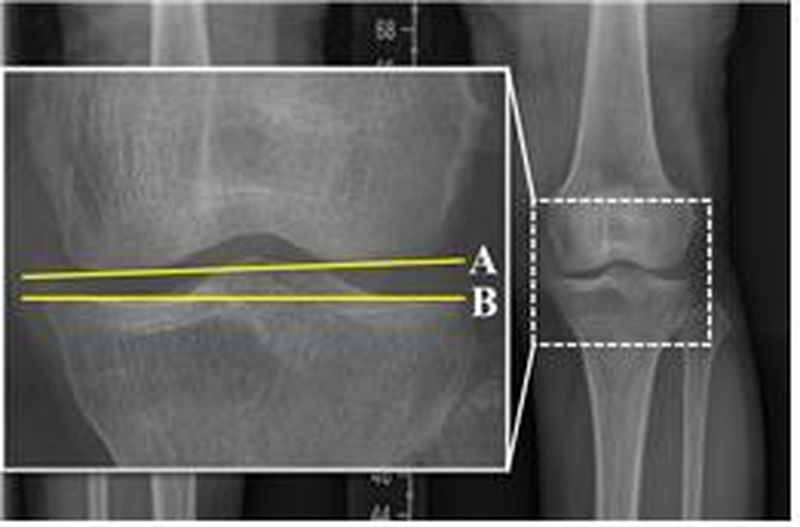

연구팀은 수술 전후 X-ray 사진을 통해 관절선 수렴각(JLCA), 무게중심선 비율(WBLR), 관절선 경사각(Joint Line Obliquity Angle) 등 다양한 방사선학 지표를 분석했다.

분석 결과 수술 전후 관절선 수렴각(JLCA) 변화(ΔJLCA)가 1.7°에서 5.6° 사이일 때 양측 무릎의 퇴행성 관절염 진행이 줄어들고 예후가 개선되는 것으로 나타났다.

또한 수술 후 JLCA가 1.5°에서 3.9° 사이의 범위에 있을 때 수술한 무릎과 수술하지 않은 반대쪽 무릎 모두에서 퇴행성 관절염의 진행과 추가 수술 위험이 가장 낮았다.